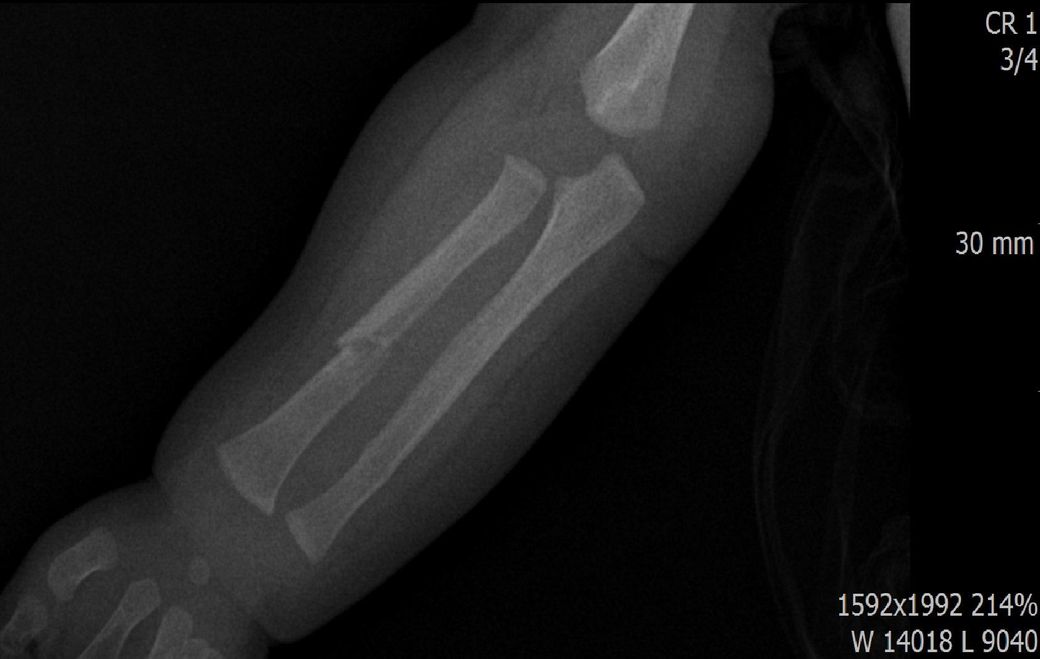

x ray 팔 골절 시기 추정해보고 싶습니다.

다름이 아니라, 첨부드린 엑스레이(X-ray) 사진처럼 골절 사실을 알게 되고 골절 발생 시점 대략적으로나마 추정시기를 파악하려고 문의 드리게 되었습니다

1) 3월 30일 촬영한 X-ray만으로 정확한 골절 시기를 100% 특정하는 데에는 한계가 있다는 점 충분히 인지하고 있기에 촬영날짜 기준으로 대략적으로 어느정도 시점에서 발생되었을 것으로 추측(ex 당일, 7~10일전, 7~14일 전, 10일 ~ 20일전, 14일 ~ 30일전 등등등)되는지 이해하고 싶습니다.

첨부드린 파일에는 없지만 4월 5일 사진에서는 캘로스 라는 것이 발견된다고 합니다.

2) 미세한 금, 탈구 등이 있는 상태에서 정복 시도할 시 완전한 골절이 되고 붓기가 부어오를 수 있는지 여부가 궁금합니다.

• 3번 째 사진